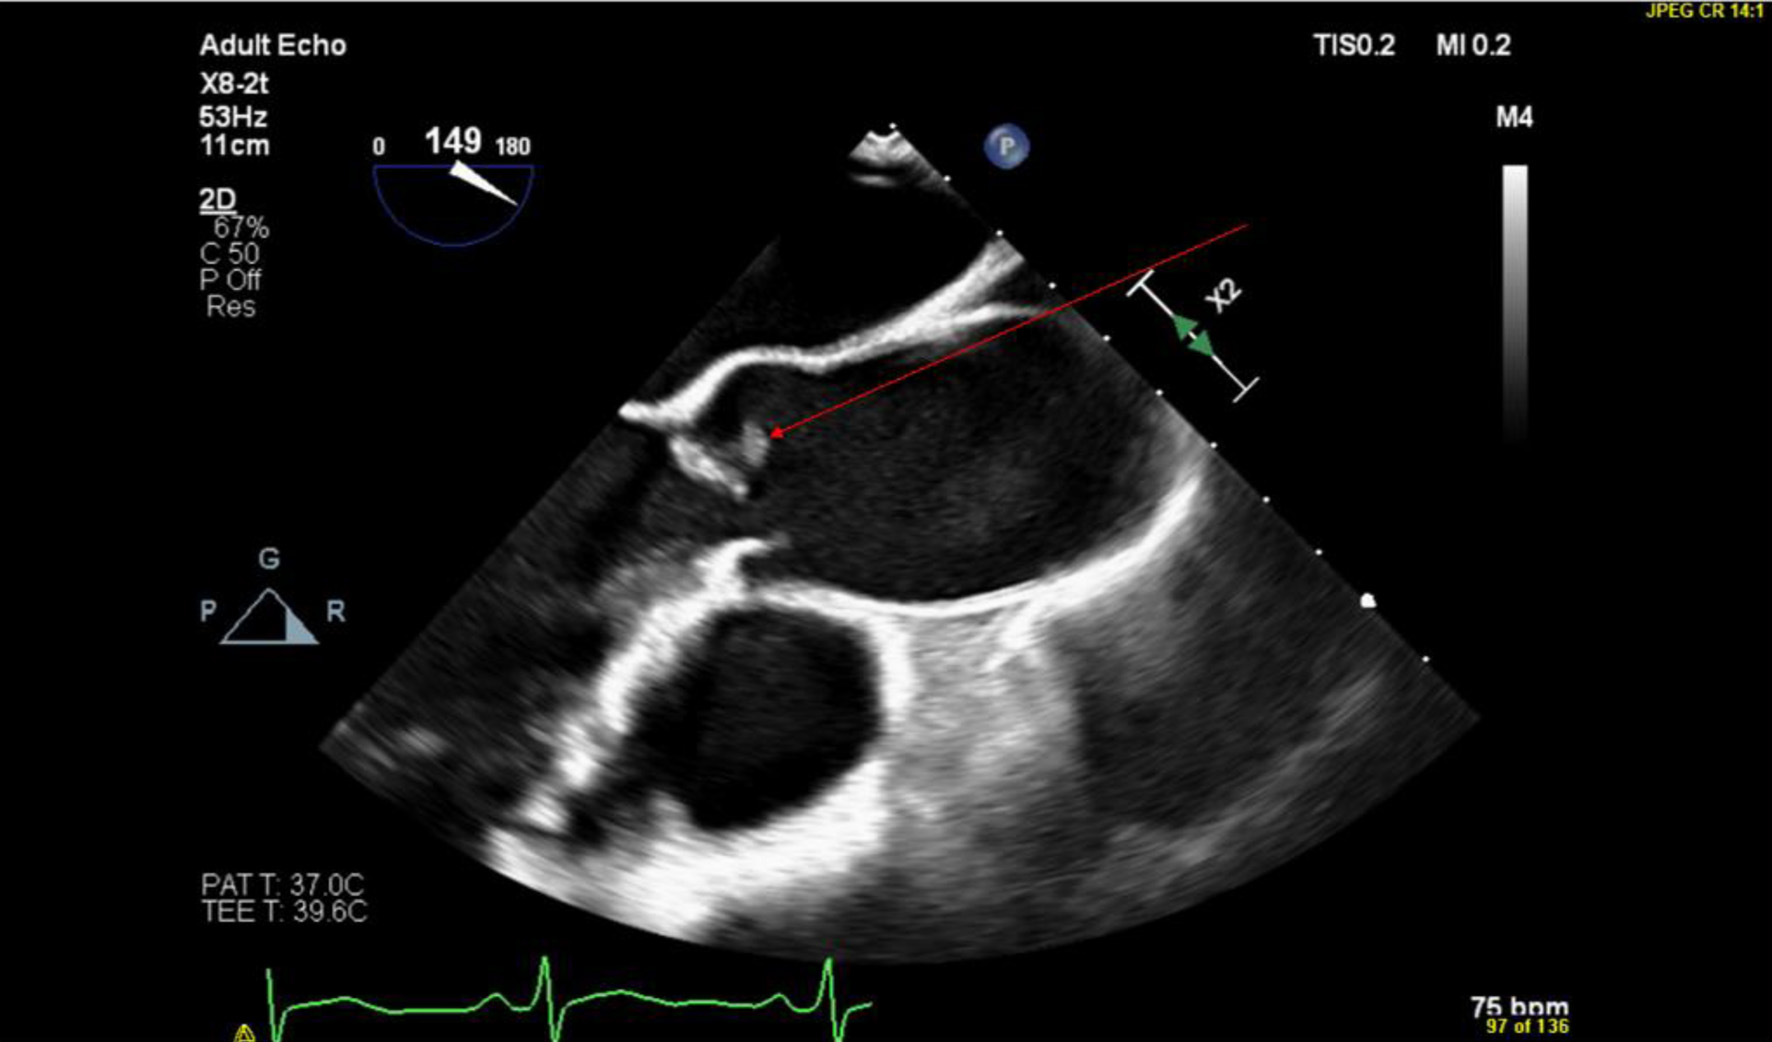

The medical team performed a holistic review of the patient’s past medical history, hospital course, and diagnostic studies. Then, the medical team discussed available treatment options with the patient to reach a decision regarding the patient’s treatment plan. With the patient’s consent, the medical team made the decision to manage the patient with long-term anticoagulation due to the difficulty of intervention on the distal apical LAD artery. The patient was discharged on apixaban. The Cardiology team followed up with the patient. A Cardionet study was performed to rule out arrythmias as a cause of the embolic phenomenon with the PFO as a conduit. The Cardionet study was mostly unremarkable, with the exception of sinus bradycardia related to beta blockers. The Cardiology team proceeded with PFO closure assessment. For better illustration of the PFO, which was demonstrated on the transthoracic echocardiography that was performed while the patient was hospitalized, the cardiology team ordered a transesophageal echocardiogram (TEE). The TEE was performed 2 months after discharge and showed a small 0.3 cm mobile echodensity on the right coronary aortic valve leaflet with stalk attachment and areas of echolucency within the tumor. These echocardiographic features were suggestive of an incidental finding of a papillary fibroelastoma on the aortic valve (Fig. 1). The TEE also demonstrated the previous finding of right to left shunting through the PFO, which was previously demonstrated on TTE.

Figure 1. TEE showing a parasternal long axis view of the aortic valve with the papillary fibroelastoma indicated by the red arrow. TEE: transesophageal echocardiogram.